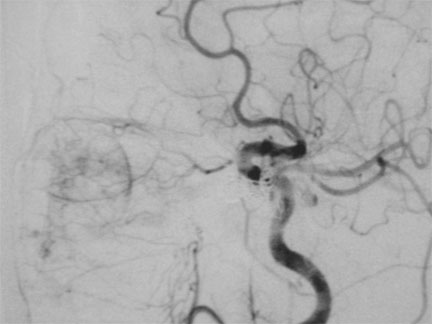

Depués de la embolización de fístula carótidocavernosa. Note el cierre de la comunicación arteriovenosa anómala, esto de la fístula carótidocavernosa

Después del tratamiento por embolización de fístula carótidocavernosa. Note desconexión de la fístula con normalización anatómica y dinámica